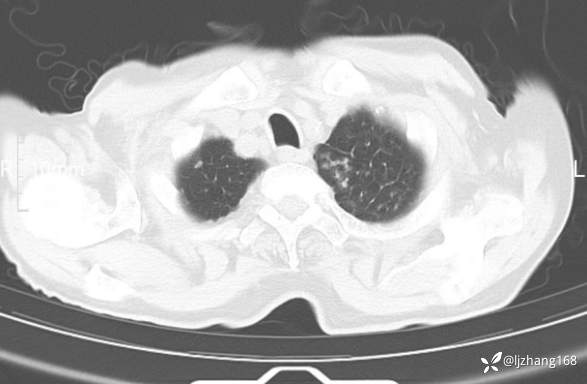

辅助检查:胸部CT:双肺肺气肿,间质性病变,血气分析:PH 7.413, PCO2 29.2mmHg, PO2,81.8mmHg,乳酸 3.3mmol/1,剩余碱-4.0mmol/1,HC03 18.8mmol/1。全血超敏C反应蛋白:超敏C反应蛋白 135.60 mg/L、 白细胞 14x19^9/L,中性粒细胞11.6x10^9/L。